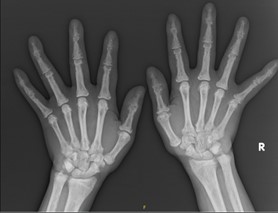

体格检查:生命体征平稳,慢性肾病面容,睑结膜略苍白,球结膜充血。心肺腹查体无异常。双手关节掌曲状态,背伸困难(图A)。双手、右下肢麻木疼痛、全身多个关节疼痛,四肢肌力5级。双下肢轻度浮肿。

入院后辅助化验检查:血常规+网织红细胞计数:血红蛋白101.00g/L,网织红细胞比率4.20%,网织红细胞绝对计数137.30*109/L;肝功生化血脂:谷氨酰转酞酶180U/L,碱性磷酸酶751U/L,腺苷脱氨酶117.80U/L,前白蛋白355mg/L,总白蛋白26.6g/L;尿素13.9mmol/L,肌酐519.90μmol/L,肾小球滤过率7.62,尿酸143μmol/L,钙1.91mmol/L,乳酸脱氢酶316.70U/L;甘油三酯1.75mmol/L,同型半胱氨酸33.20μmol/L;贫血指标六项:内因子抗体1.25AU/ml,总铁结合力49.70μmol/L;甲状旁腺素835.00pg/ml;凝血五项:D-二聚体5.49mg/L,纤维蛋白(原)降解产物16.56μg/ml,纤维蛋白原4.72g/L;PRO-BNP:1876.00pg/ml。病毒定量+梅毒抗体、粪便常规+沉渣+隐血未见异常。腹部超声:双肾萎缩,呈弧形强回声改变。上肢血管超声:右前臂桡动脉-头静脉造瘘术后。心脏超声、眼科检查未见明显异常。双手DR正斜位(图B):双手骨质改变,结合病史,考虑肾性骨病(骨膜下骨吸收)。

2025.07.03-07.12行硫代硫酸钠3.2g/d*10d静滴,治疗约1周后后患者双手关节可背伸(图I),双手及右下肢麻木疼痛消失,各关节疼痛明显减轻。